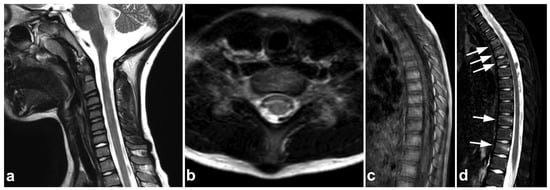

7.4. Imaging Appearances of Normal Skeletal Maturation

Every radiologist performing pediatric imaging must be aware of the fundamentals of skeletal maturation [87]. On the MR imaging of acute pediatric trauma, one of the potential pitfalls is the physiological high T2 signal at the physis and metaphyseal spongiosa of the secondary ossification centers [88]. This can be misinterpreted as traumatic edema if the normal anatomy and development of the ossification centers are not kept in mind (Figure 20). On the other hand, an unfused vertebral ring apophysis [89,90], apophyseal injuries [91], and other calcifications not related to the acute injury are readily distinguished from fractures with the absence of edema (Figure 21).

Figure 20.

(a) Axial fat-suppressed T2-weighted. (b) Coronal STIR. An 11-year-old male, lower back/pelvic pain after falling on ice. MRI demonstrates symmetric zones of bright T2 signal (arrows) at the secondary ossification centers of the sacrum and iliac bone, characteristic of normal skeletal maturation. With the symptoms and injury mechanism in such a case, the findings could be misinterpreted as traumatic edema if the normal skeletal maturation and anatomy of the ossification centers are not kept in mind.

Figure 21.

(a) NECT, coronal reconstruction with a bone kernel. (b) NECT, sagittal reconstruction with a bone kernel. (c) Sagittal STIR. (d) Coronal STIR. A 9-year-old male, neck pain and midline cervical tenderness after diving into shallow water. Small osseous fragments were seen at the anteroinferior corners of vertebral bodies C5 and C6 (arrows). The imaging appearance was consistent with inferior ring apophyses, but due to cervical spine symptoms and high-risk injury mechanism, MRI was performed. STIR imaging did not show any edema, neither in the proximity of the ring apophyses nor elsewhere in the spine. The apophyses were not visible at MRI.